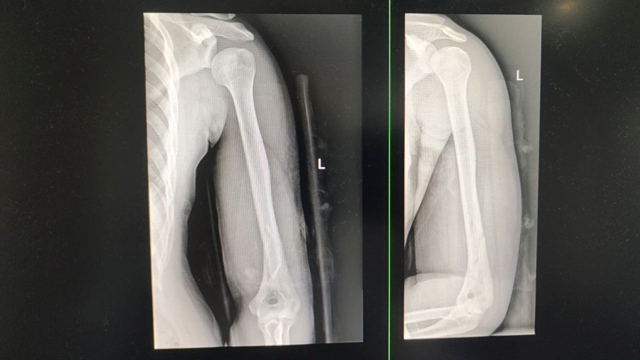

林浩被立即送往当地医院就诊,完善X光检查提示:左肱骨骨折。医生立即予以对症止痛、石膏外固定+三角巾悬吊治疗。医生看着林浩的X光片,惋惜地说到,“哎,骨头断了,需要开刀上钢板才行。”

科室王念武主治医师接诊后,详细检查了林浩的手臂,查看了X光片,发现林浩的骨折为闭合性骨折,虽然肿胀严重,但没有神经血管损伤,手法复位后能达到复位标准,则不影响后期功能恢复,且患者才23岁,新陈代谢能力强,恢复快,可以采用中医正骨保守治疗。

医生立即进行手法复位,在助手的默契配合下,只见王念武气定神闲,手法娴熟地施展起中医正骨绝技 ——“一牵,二折,三顶”。他的双手精准发力,一牵之下,骨折处间隙被巧妙拉开,为复位创造条件;紧接着顺势一折,瞬间纠正骨折错位;最后轻轻一顶,骨折断端严丝合缝,整个过程一气呵成,如行云流水般顺畅自然,眨眼间,骨折部位便完美复位。

随后,王念武小心翼翼地为林浩外敷上医院独具特色的中药制剂,具有消肿止痛、活血化瘀、促进骨骼生长的功效。敷药完毕,再用杉树皮进行夹板固定,为受伤的手臂提供稳定支撑,确保复位效果。进行一段时间康复训练后,林浩的手臂便基本可以恢复如初。